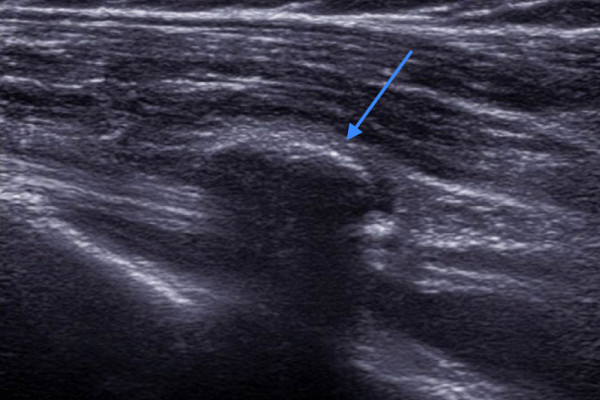

Diese Bild zeigt ein Kalkdepot über der Bizepssehne (Pfeil), typisch ist, daß die Schallwellen komplett durch den Kalk reflektiert werden und man unter dem Kalk nichts mehr erkennen kann.